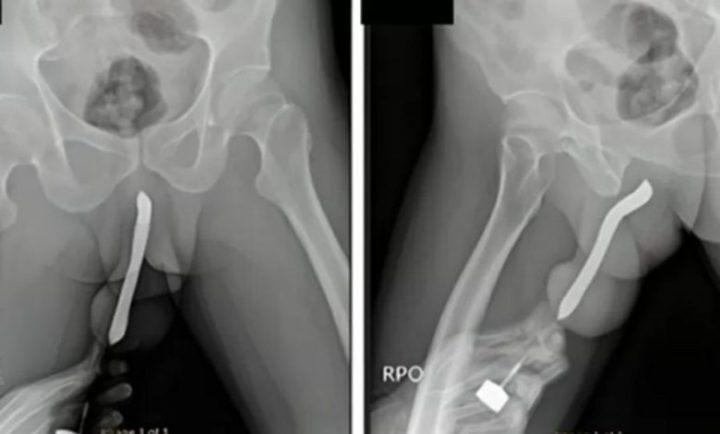

Ao chegar ao hospital, ele apresentava sintomas como dor intensa, inchaço e hematomas. Os médicos confirmaram a presença do objeto através de exames de imagem, e ele foi submetido a uma cirurgia de remoção. Após o procedimento, o paciente se recuperou bem e recebeu alta três dias depois.